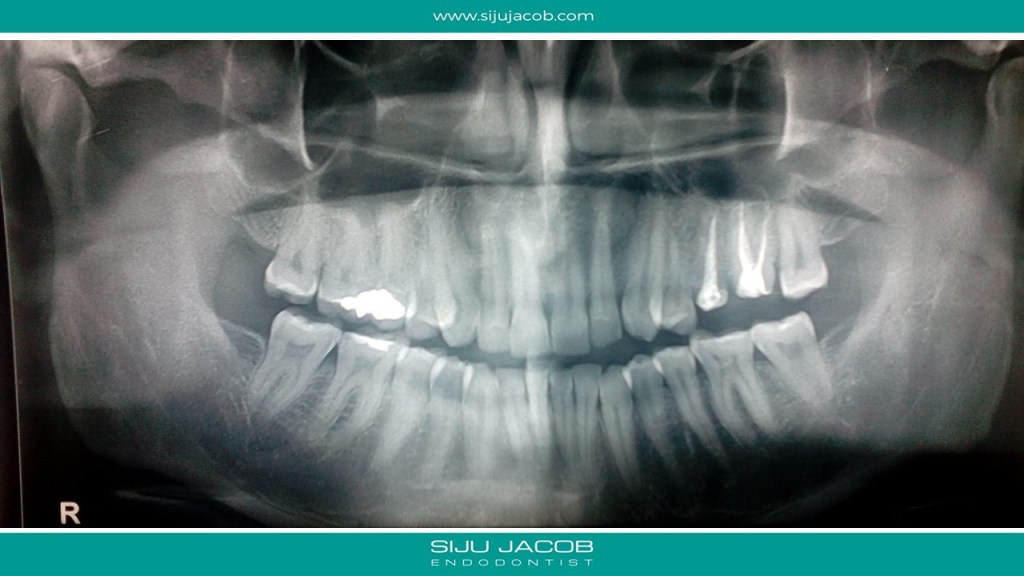

I told her to come and see me for a consultation. I didn’t hear from her for a month. After a month, i received another mail saying that the dentist who did the earlier Root canals had offered to re-do both the root canals and she had gone ahead. She said that she still had discomfort in both teeth. She sent me these images.

I told her to drop in for a consultation with me. Two months later, i get another mail telling me that her dentist had placed new crowns in both the teeth, but she was still not comfortable. The dentist had then offered to call in another specialist to re-do the root canal in one of the teeth. He had started the Re-root canal procedure, but the pain was still not gone. Could I have a look? She finally landed in my clinic and this is what i saw. And hence the title of the post: Oh No!